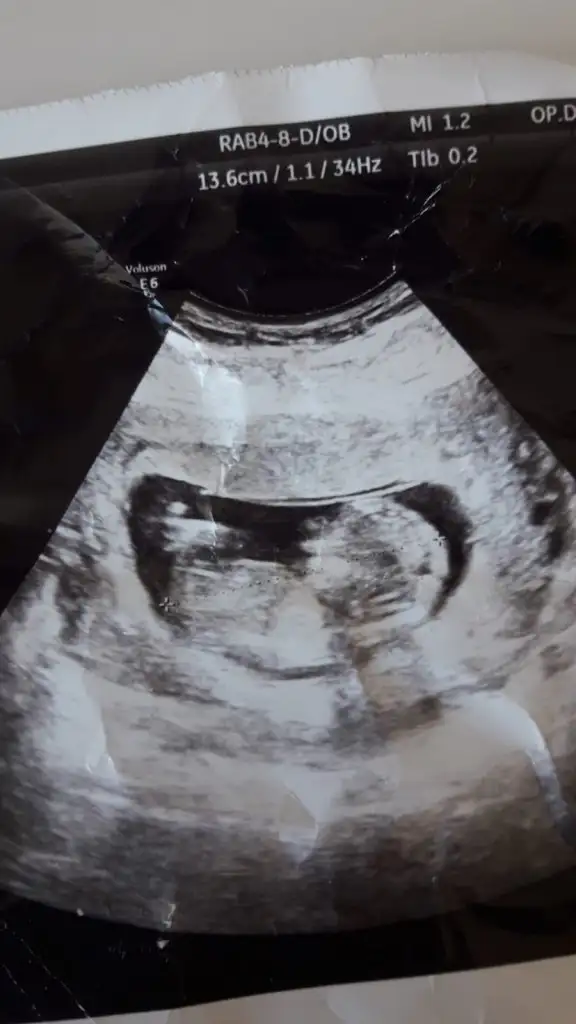

Kiz gibi görünüyorMerhabaIkra meyra benım tahminime kız demiştiniz tuttu, buda eltimin 13 haftalık sizce bebeğimiz nedir ???

Bu usgde ise 11-12

Eki Görüntüle 2935644